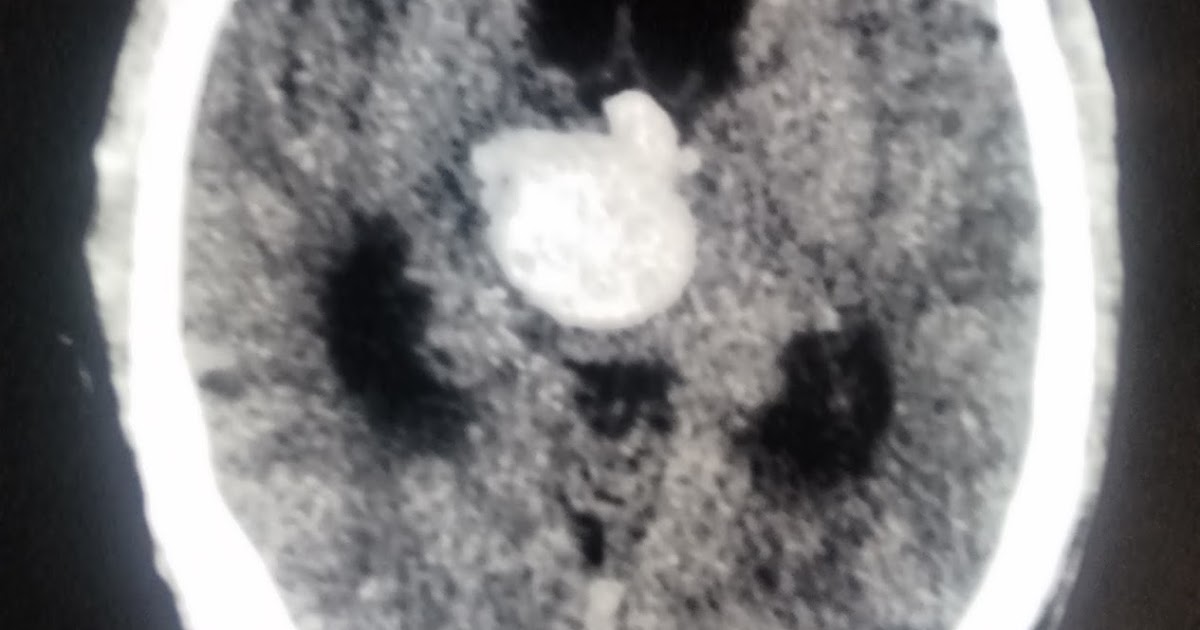

CT image of thalamic hemorrhage. Download Scientific Diagram Thalamic Hemorrhage Icd-10 A hereditary disease that slowly deteriorates the brain. For clinicotopographic analysis, we determined four types of thalamic hemorrhage, as described elsewhere: Bleeding into one or both cerebral hemispheres including the basal ganglia and the cerebral cortex. Thalamic hemorrhage is the second most common location of nontraumatic intracerebral hemorrhage, accounting for 10% to 15% of all hemorrhages. People with this disease. Thalamic Hemorrhage Icd-10.

CT image of thalamic hemorrhage. Download Scientific Diagram Thalamic Hemorrhage Icd-10 Bleeding into one or both cerebral hemispheres including the basal ganglia and the cerebral cortex. I61.8 is a billable diagnosis code used to specify a medical diagnosis of other nontraumatic intracerebral hemorrhage. The code is valid during the current fiscal year for the submission. People with this disease get panic attacks, paranoia, and phobias. Thalamic hemorrhage is the second most. Thalamic Hemorrhage Icd-10.